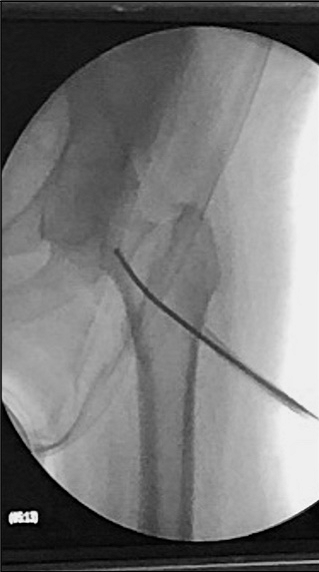

Actualmente tenemos la posibilidad de mejorar la resistencia del hueso y prevenir las fracturas de las personas mayores. Lo hacemos con una simple inyección dentro del hueso de una sustancia cálcica especial (OSSURE LOEP) que le fortalece y estimula la regeneración del hueso propio. Este efecto es inmediato, a diferencia de la medicación, que tarda meses o años en conseguirlo.

El producto OSSURETM LOEP se INYECTA EN EL HUESO para RELLENAR Y formar hueso nuevo en áreas del esqueleto OSTEOPOROTICO QUE PRESENTA MULTIPLES PEQUEÑAS CAVIDADES VACIAS. ESTE material biorreabsorbible, Y osteoconductor ESTÁ HECHO A BASE DE CALCIO. El procedimiento de mejora ósea local es un procedimiento mínimamente invasivo. Se inyecta en sitios preparados quirúrgicamente OSSURE donde se endurece, se reabsorbe y se reemplaza con hueso nuevo.

El procedimiento suele durar menos de 30 minutos.